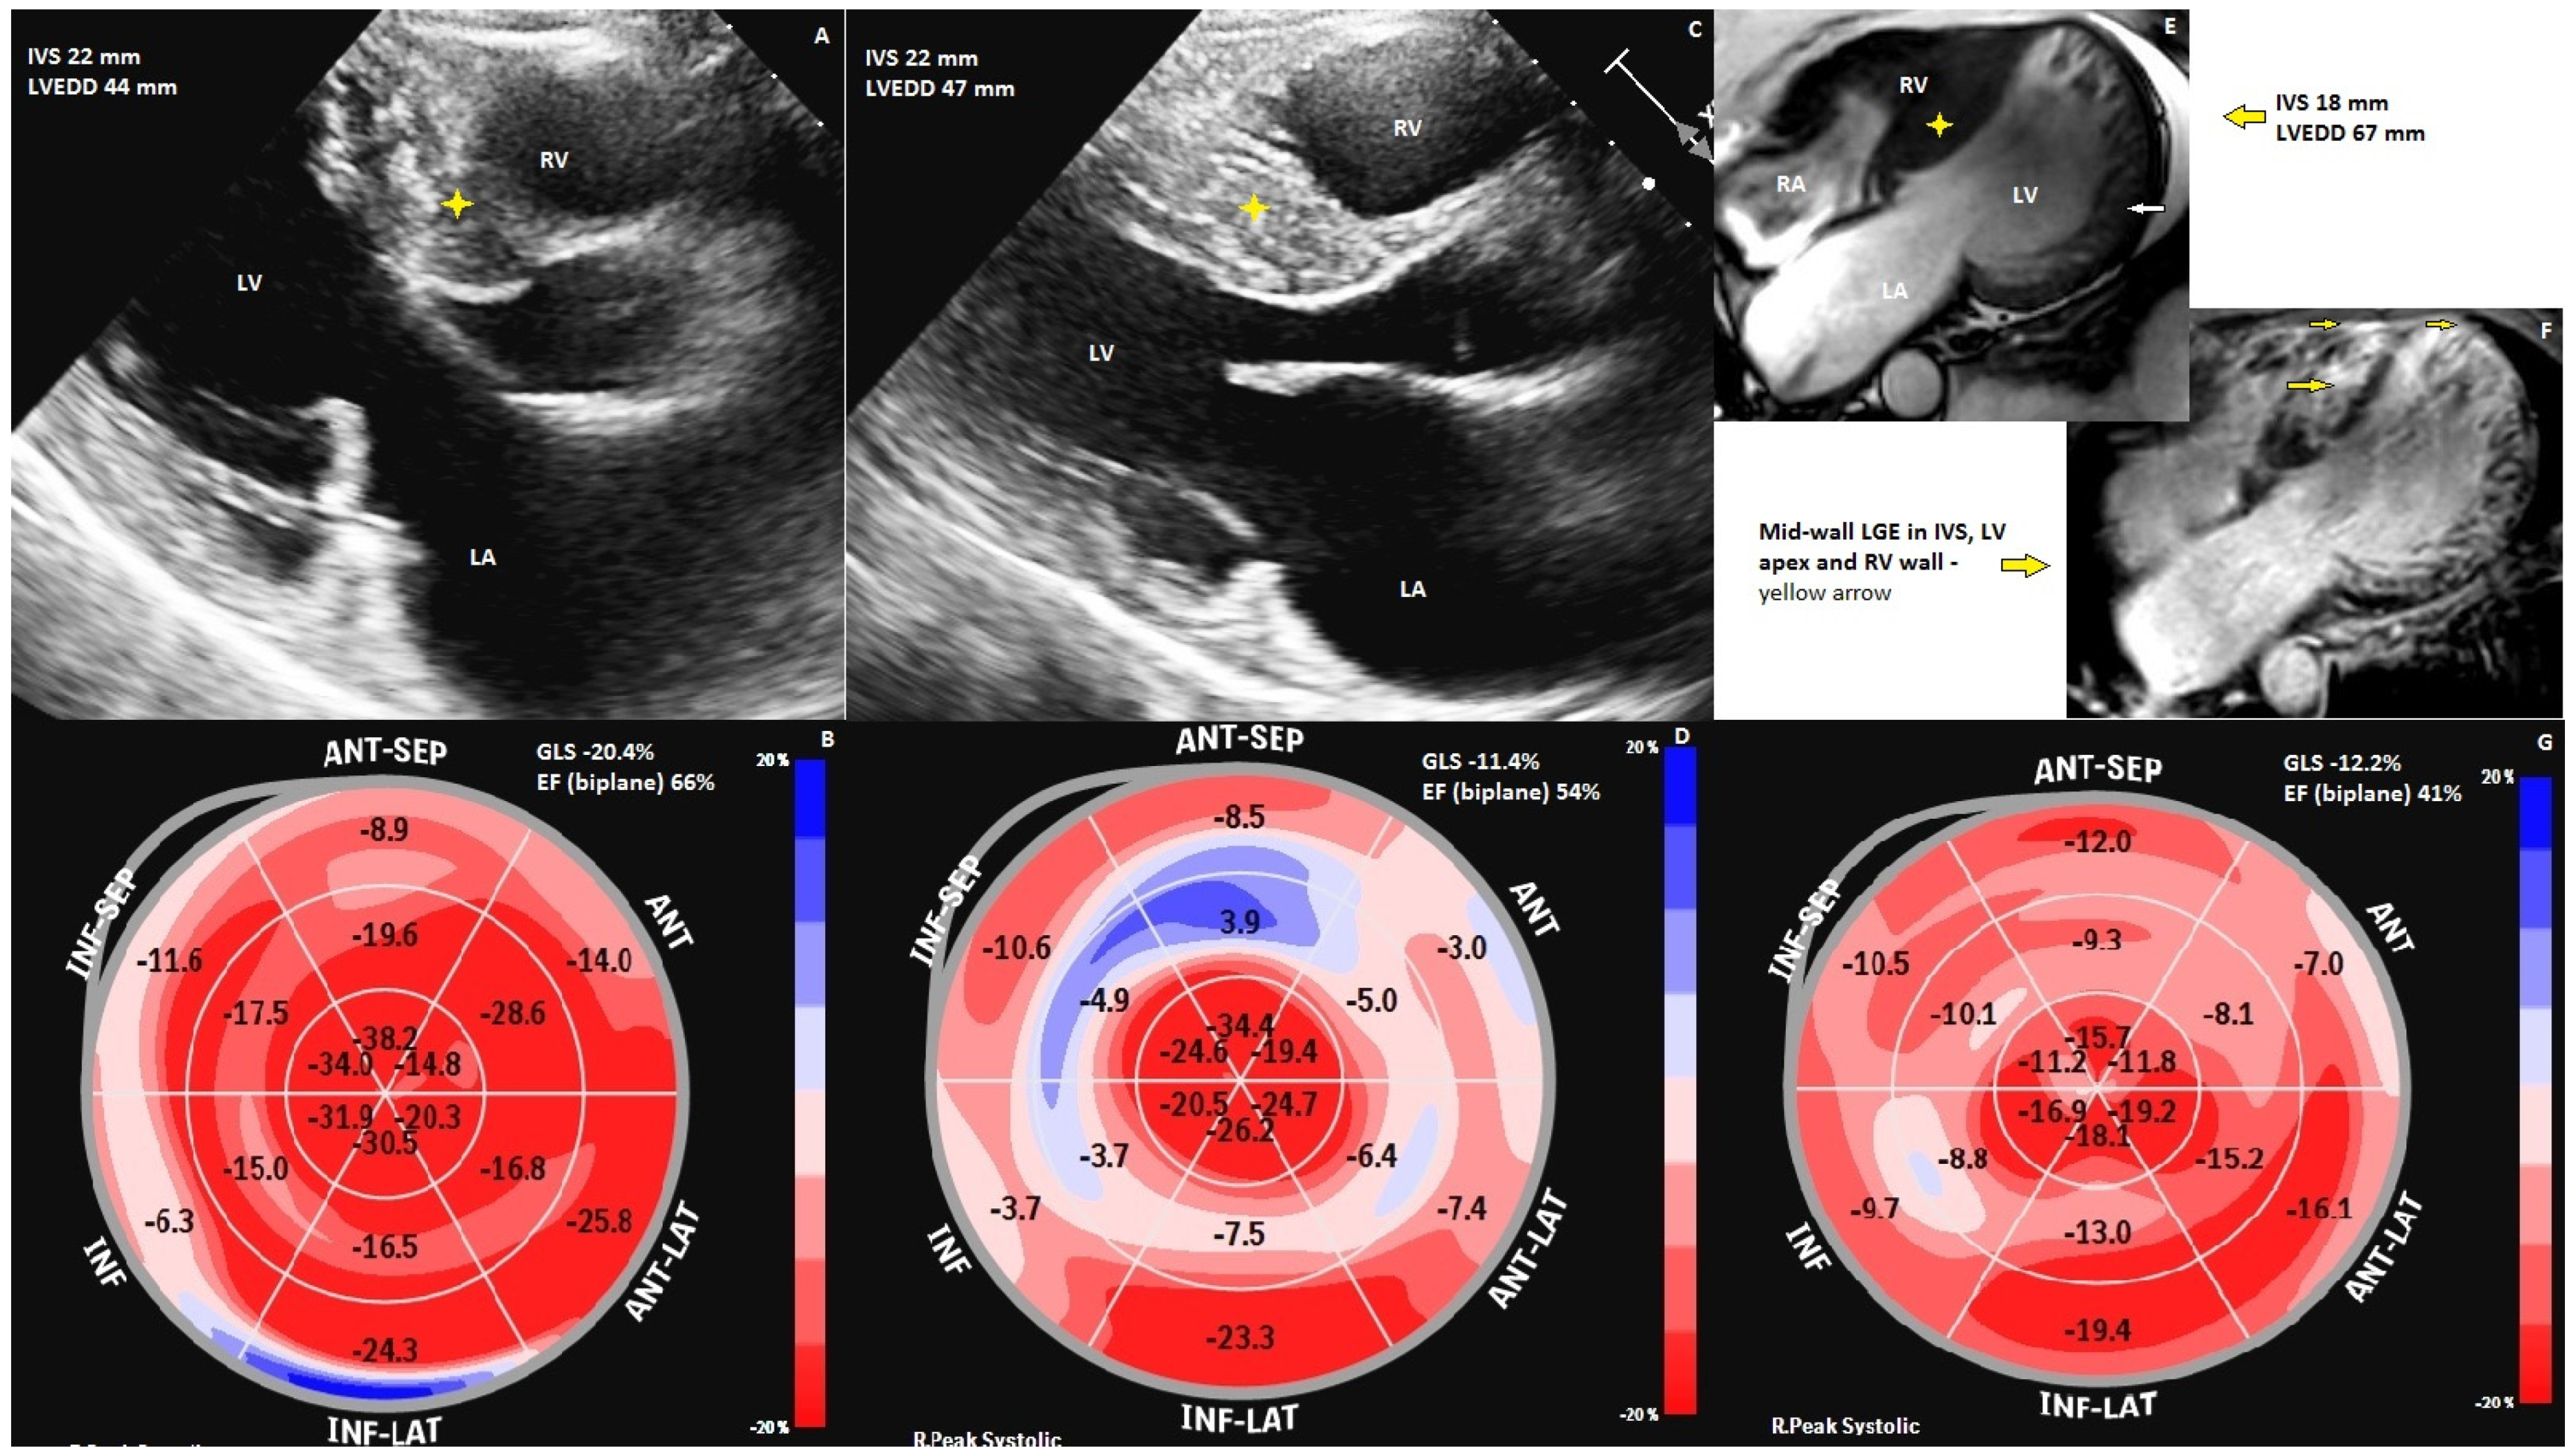

In Case 1, the proband (Figure 2E–G) is a 42-year-old male, without significant medical history, who was admitted for heart failure symptoms; imaging evaluation by transthoracic echocardiography (TTE) showed a dilated left ventricle of 67 mm, a mildly reduced ejection fraction, aspect of non-obstructive HCM (SAM absent), and moderate mitral regurgitation. Global longitudinal strain bull’s eye imaging showed reduced global longitudinal strain (−12.2%) with an ejection fraction of 41%, and 64 ms mechanical dispersion. Cardiac magnetic resonance (cMR) revealed aspects of non-obstructive HCM and criteria for left-ventricular noncompaction (with a 3.7 non-compacted/compacted ratio by Jenny criteria evaluated using CMR) [8]. The cardiac magnetic resonance imaging SSFP-cine sequence four-chamber view displayed bi-ventricular hypertrophy with asymmetric LV hypertrophy, IVS predominance (IVS 18 mm), an RV free wall of 9 mm, dilated left ventricle, and global hypokinesia. It was also noted that there was important trabeculation of the left ventricle apex, lateral, and anterior walls. Cardiac magnetic resonance imaging late gadolinium enhancement showed mid-wall enhancement in the IVS, LV apex, and RV (right ventricle) wall. 24 h Holter-EKG monitoring revealed polymorphic ventricular ectopies with high arrhythmic loading, and the 5-year-risk of SCD calculated with the 2014 ESC HCM-risk-SCD calculator was 5.48%. The patient had an ICD implant as primary prophylaxis for SCD. At the one-year follow-up, the ICD recordings showed four non-sustained VTs with no need for therapies; also, the patient suffered a minor ischemic stroke with no clear origin of the thrombus.

Case 2 (Figure 2A,B) is a 55-year-old woman presenting heart failure symptoms two years prior to the cardiovascular examination. The ECHO parasternal long-axis view revealed asymmetric left ventricle hypertrophy with the predominant interventricular septum (IVS) hypertrophy of a maximum of 22 mm. The resting LVOT gradient was 20 mmHg and the provoked gradient was 33 mmHg. The mitral valve had moderate regurgitation, with a vena contracta of 6.2 mm, and SAM was absent. Global longitudinal strain bull’s eye imaging showed normal global longitudinal strain (GLS) and preserved ejection fraction, with reduced regional longitudinal strain predominantly in the basal segments of the IVS and inferior wall. Despite a normal GLS value (−20.4%) and low values of mechanical dispersion (36 ms), the patient presented three episodes of VT. She was diagnosed with obstructive HCM and a 5-year risk of SCD of 4.02% calculated with the 2014 ESC HCM-risk-SCD score, and she received an implantable cardioverter–defibrillator (ICD) as primary prophylaxis. At the first year of follow-up, the device recordings showed three asymptomatic episodes of non-sustained VT, one of them treated with anti-pacing therapy (ATP). The important arrhythmic burden could be explained by the basal inferior segment of the LV that has a decreased regional GLS, probably because of important fibrosis. The ECHO should be correlated with cRM for better comprehension. Her 11-year-old daughter, diagnosed with HCM, had an ICD implanted when she was 9 years old for sustained polymorphic ventricular tachycardia (VT).

Case 3 (Figure 2C,D) is the oldest brother, a 47-year-old male with a history of surgical myomectomy (2014) for obstructive HCM and cryoablation for paroxysmal atrial fibrillation (2018). ECHO after the surgical myomectomy revealed in the parasternal long-axis view asymmetric left ventricle hypertrophy with predominant IVS hypertrophy of a maximum of 22 mm, SAM was absent, and mild eccentric mitral regurgitation. Global longitudinal strain bull’s eye imaging showed reduced GLS (−11.4%) despite preserved ejection fraction; the regional longitudinal strain was severely reduced in the mid and basal segments of the interventricular septum, left ventricle anterior, and inferior walls. Despite a low GLS value and a high value of mechanical dispersion of 80, the patient did not present episodes of VT. The low values of GLS and high values of mechanical dispersion could be explained by the myocardial scar secondary to myomectomy. The 5-year risk of SCD of 7.5% was calculated with the 2014 ESC HCM-risk-SCD calculator SCD and prophylaxis with an ICD implant was performed (2017). The ICD did not record any rhythm disturbance after ablation.

Figure 2. Imaging of hypertrophic cardiomyopathy of the three siblings. (A) ECHO of the 2nd patient, parasternal long axis 5 chambers; (B) ECHO of the 2nd patient, bull’s eye displays of GLS; (C) ECHO of the 3rd patient, parasternal long-axis view; (D) ECHO of the 3rd patient, bull’s eye displays of GLS; (E) cMR of the proband, showing the trabeculations in end-systole; (F) cMR of the proband, showing late gadolinium enhancement in LV wall, RV wall and interventricular septum; (G) ECHO of the proband, bull’s eye displays of GLS.